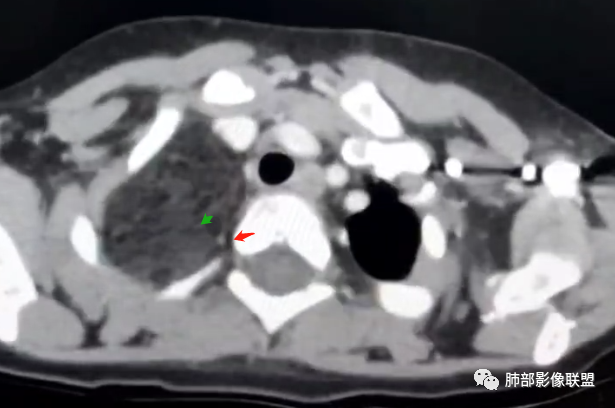

定位:肺内?尖段气管未见明显显示,腔静脉受压向右推移?病灶内可见前段动脉穿行,脂肪密度为主。

肿块起源于右上气管分叉处?强化动脉血管最后汇入右肺动脉上干。

右侧纵隔奇静脉水平起源?压迫上肺,包绕动脉?

右肺门上方,位于纵隔胸膜旁见巨大肿块,脂肪为主混合密度,内见细小血管影,肿块最大长径与纵隔胸膜平行,包绕右肺上叶肺动脉,右肺上叶及纵隔结构推压,无侵蚀破坏,良性肿瘤,起源纵隔胸膜血管平滑脂脂肪瘤。

病灶属于交界区,主体位于肺内,占位效应明显,前方突入胸壁,胸腺受压变形,胸膜显示欠清楚;病灶包绕上叶肺动脉;似乎有体动脉供血。符合肺内的点:包绕上叶肺动脉分支;符合纵隔的点:前方似乎突入胸壁,与胸腺关系比较密切,但是与上腔静脉的关系提示病灶不支持纵隔来源,前纵隔的常规会将上腔静脉受压后移、外移,这是不符合的。

2.肺动脉穿行也许是肺内来源最重要支持点!